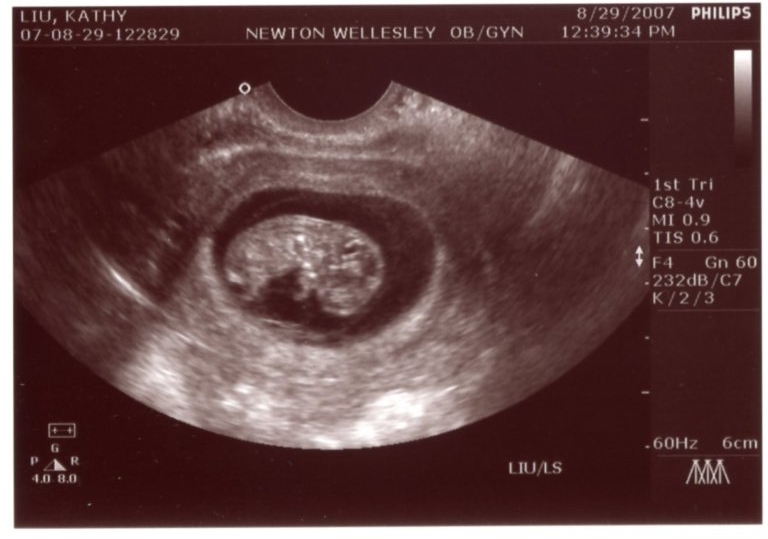

By the beginning of August, Jon was constantly bugging Kathy to take a home pregnancy test. She kept putting it off because first he was in Europe for work, then they went on a cruise to Bermuda with the Liu's, and then Jon was off to China. When Jon finally stopped traveling all over the globe, Kathy finally took the test - which was instantly positive (no need to wait the requisite 3 minutes!). After a confirmation test with Kathy's primary care physician, then there was a scamble to find an obstetrician (thanks, Anne B!) and make the first appointment. Basically, since we had no idea WHEN we got pregnant, Kathy got an appointment right away to get an ultrasound to judge how far along the baby already was. It turns out we were 9 weeks along (the fetus was about 3 cm long). When Jon saw the pictures, he began referring to the baby as his "beanie baby" since it looked like a bean to him.